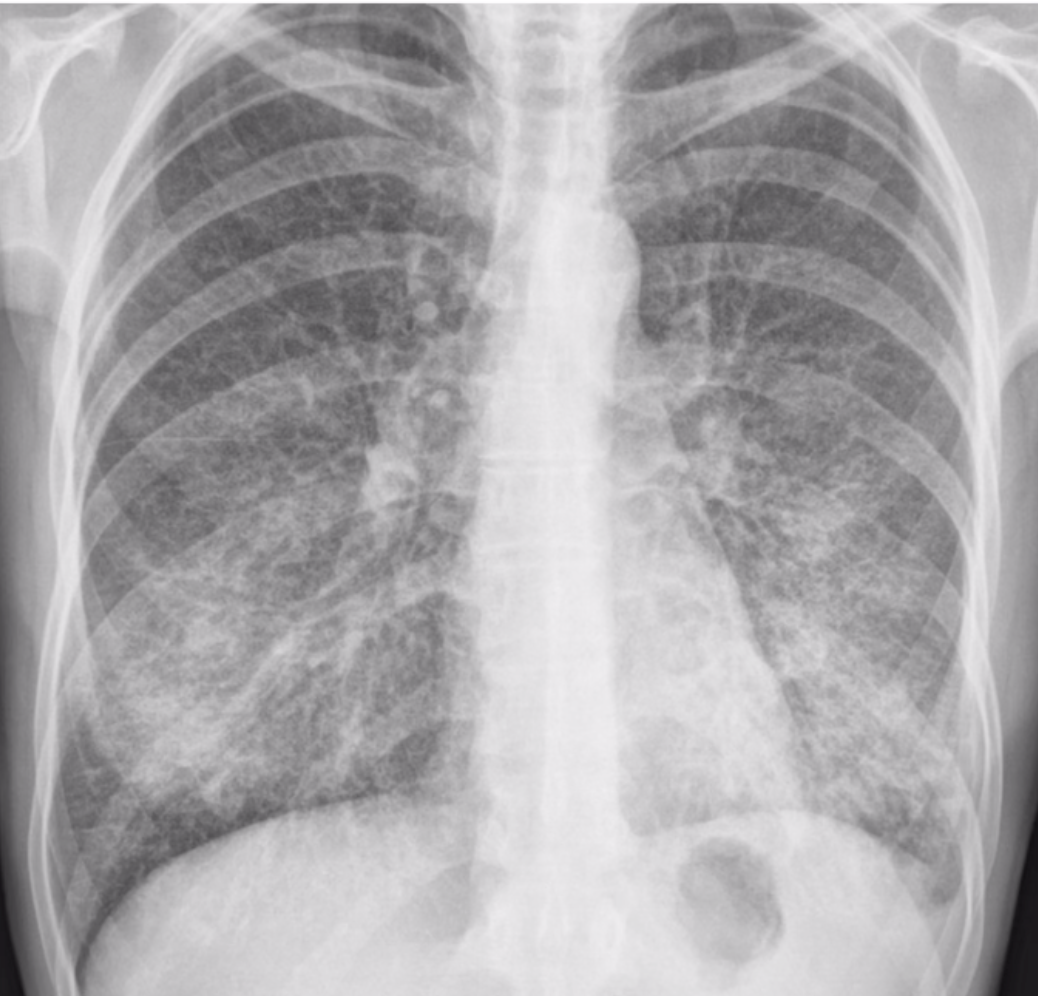

15

Q

M20a llega porque tiene fatiga hace una semana. Siente escalofríos y tiene tos seca.

TA: 120/70, FC: 92, FR: 22, T: 37.8°C, SatO2: 90%

Exploración: Estertores en ambas bases pulmonares. ¿Microorganismo responsable?

16

Descripción

A

Patrón reticular fino en ambos pulmones.